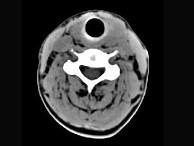

问题 40岁,女性患者,双侧甲状腺肿大,CT扫描如图所示,请选择最佳答案 ( )

选项 A、亚急性甲状腺炎 B、甲状腺瘤 C、甲状腺癌 D、甲状腺炎(桥本) E、弥漫性甲状腺肿

答案 D